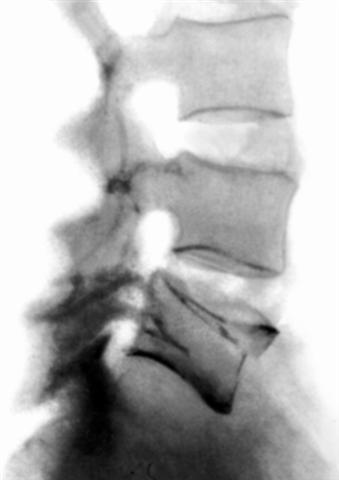

Рис. 9. Рентгенограмма нижнегрудного отдела позвоночника (боковая проекция) при переломовывихе.